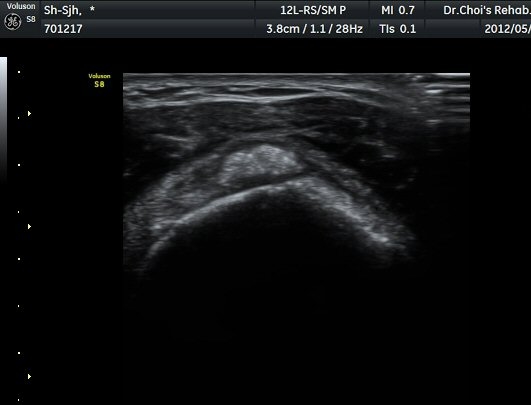

Á߸³»óÅ ¾î±ú ¾Õ Ⱦ´Ü¸é°Ë»ç¿¡¼­ À̺ειڱ٠ÁÖÀ§¿¡ ¼ö¾×Àú·ù°¡ °üÂûµÇ°í(»çÁø 1) ÆÄ¿öµµÇ÷¯

°Ë»ç¿¡¼­ Ç÷·ùÁõ°¡°¡ °üÂûµÈ´Ù(»çÁø 2). À̵ιڱ٠Á¾´Ü¸é°Ë»ç¿¡¼­µµ °Ç ÁÖÀ§ ¼ö¾×Àú·ù°¡ È®ÀÎ